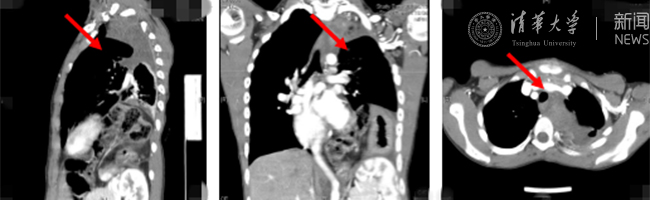

官方入口网8月30日电(通讯员 杨峰)如图中所示,本是正常人心脏、左肺的位置,被发于神经鞘的巨大肿瘤占据,导致一位刚满12岁的男孩胸痛、咳嗽、呼吸困难。近日,北京清华长庚医院神经外科与胸外科联手,由神经外科王贵怀主任主刀,成功为男孩切除胸腔巨大神经鞘肿瘤。

患者胸腔内巨大的肿瘤。

半年前,患者经常会出现胸痛、咳嗽和呼吸困难,在当地医院检查发现左侧胸腔巨大占位,左肺及心脏明显受压。王贵怀大夫接诊,仔细查体了解病情,并反复认真阅片后,认为左侧胸腔巨大肿瘤来自于胸椎椎管内,神经鞘瘤可能性大。该肿瘤体积巨大,占据绝大部分胸腔空间,压迫左肺、纵隔大血管及膈肌。